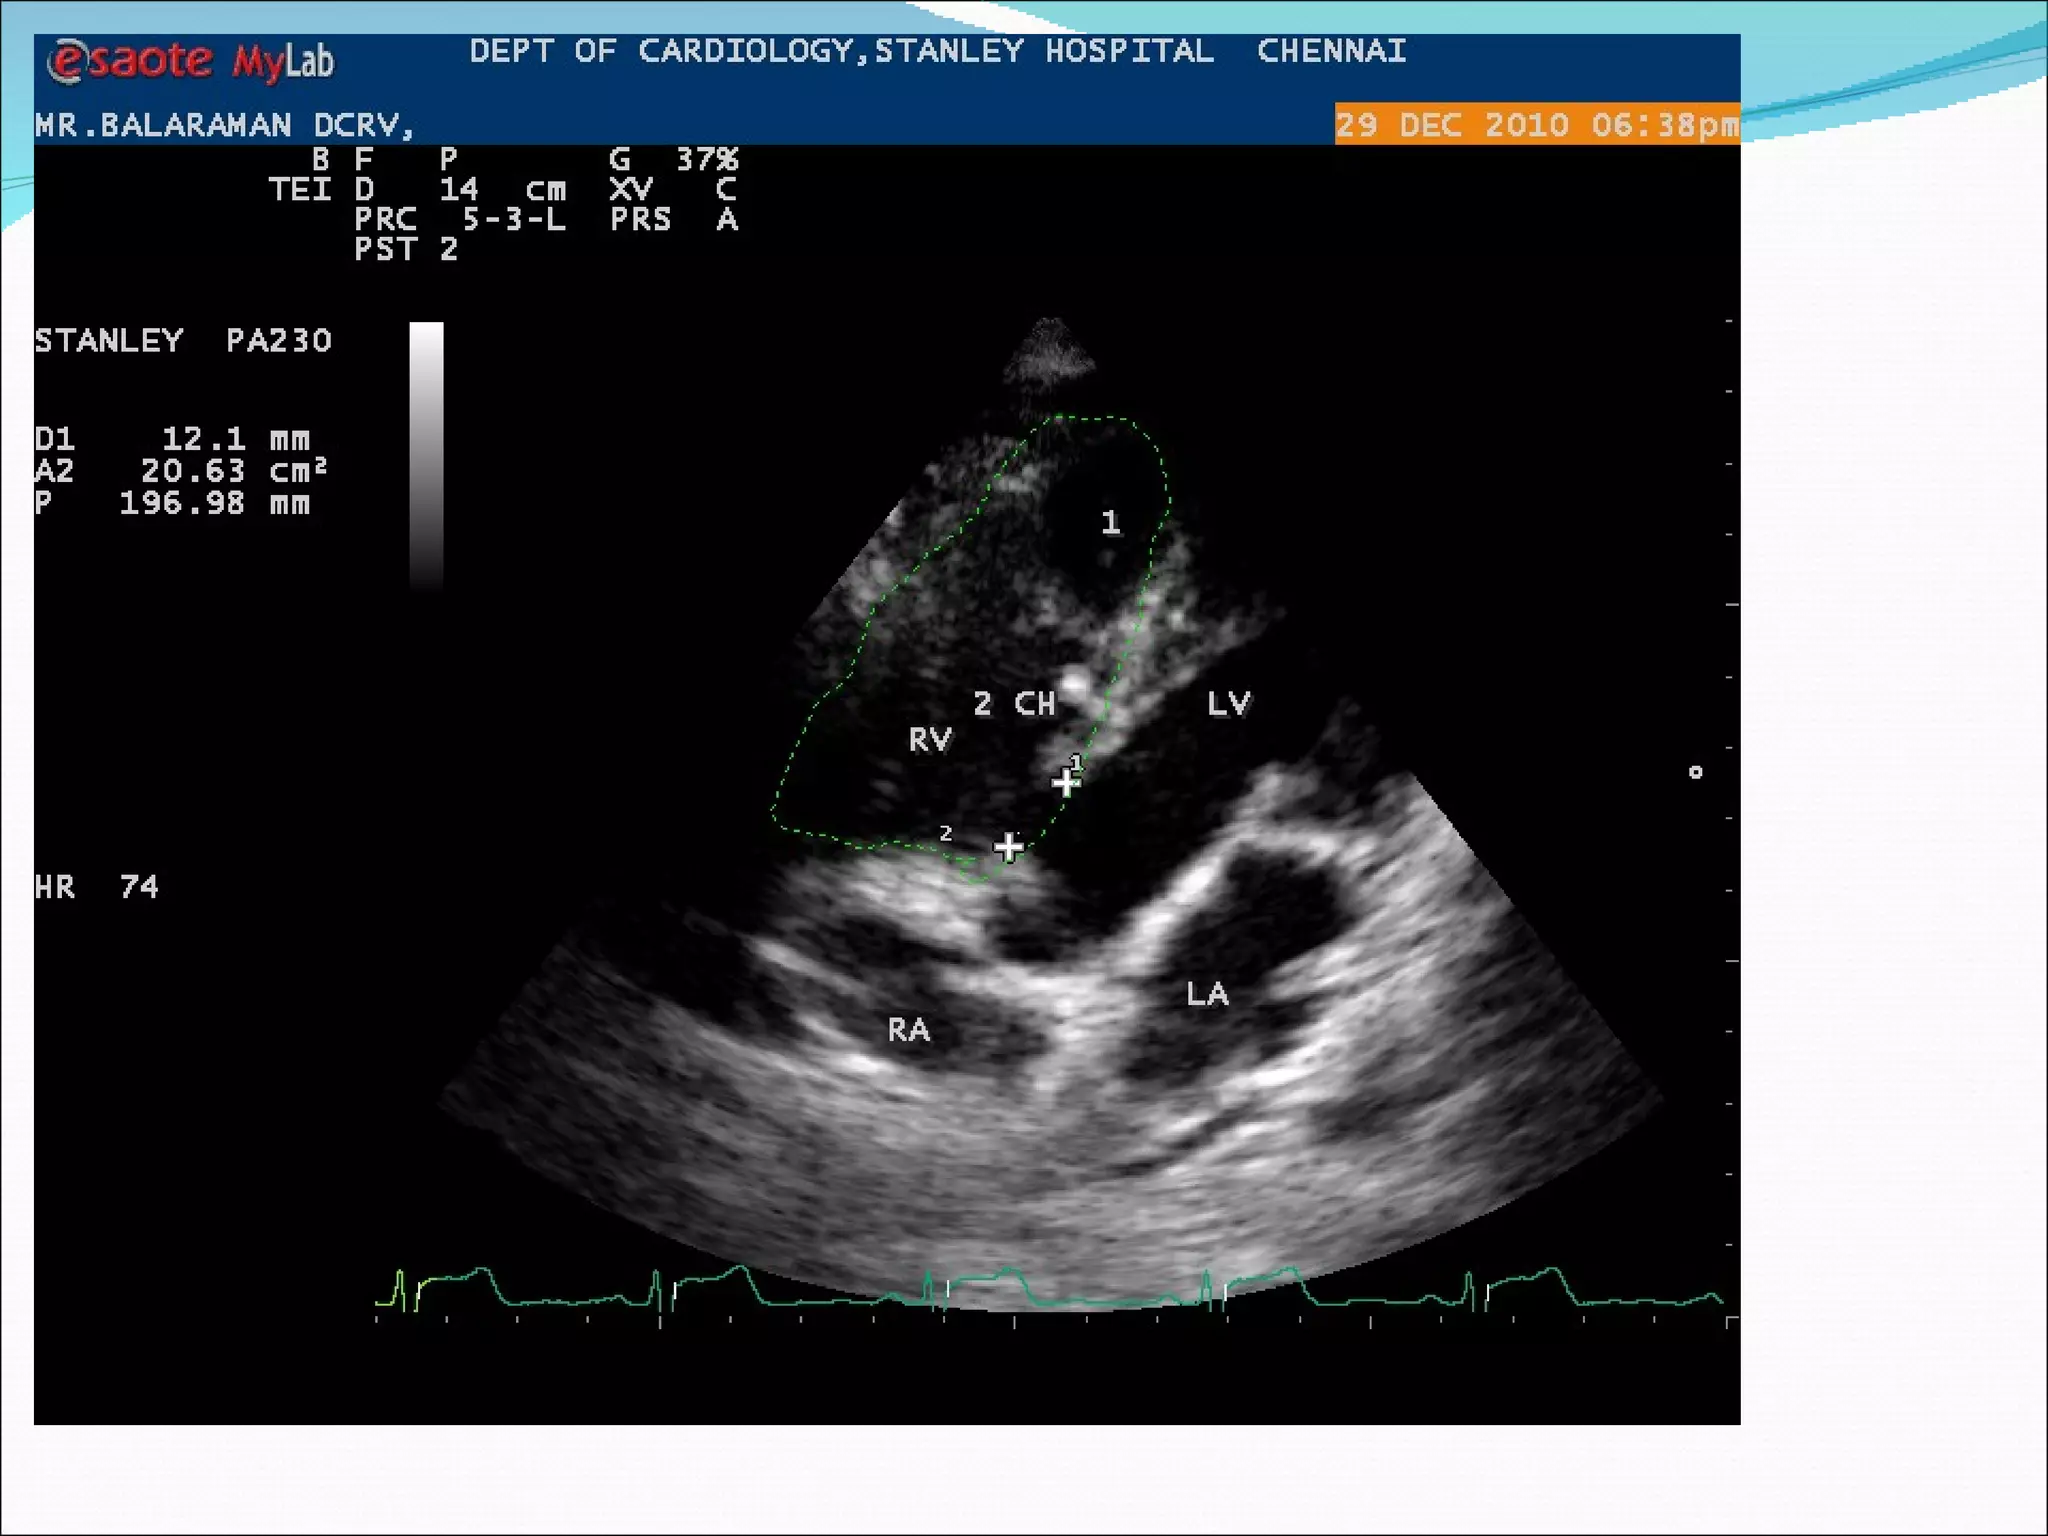

A 20-year-old male patient presented with complaints of palpitations and exertional breathlessness. On examination, he had a heart rate of 64 beats per minute, blood pressure of 100/70 mmHg, and a grade 5/6 pansystolic murmur heard best over the left parasternal area. An ECG showed right ventricular hypertrophy and right axis deviation. An echocardiogram confirmed the diagnoses of a ventricular septal defect and double chambered right ventricle.